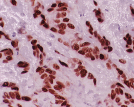

Imunocitoquímica

É uma técnica que permite identificar componentes celulares específicos através de reações antigénio-anticorpo. É importante para o completo diagnóstico anatomopatológico, bem como para orientação terapêutica.

No SAP-CHLO dispomos de técnicas de imunohistoquímica, hibridização in situ e PCR em tempo real, esta última aplicável em tumores sólidos e sangue periférico (biópsia líquida). Estas técnicas permitem a pesquisa de mutações genéticas no cancro, identificando aqueles que são susceptíveis de serem alvo de terapêuticas personalizadas, levando a melhores resultados terapêuticos e maior qualidade de vida para os doentes.